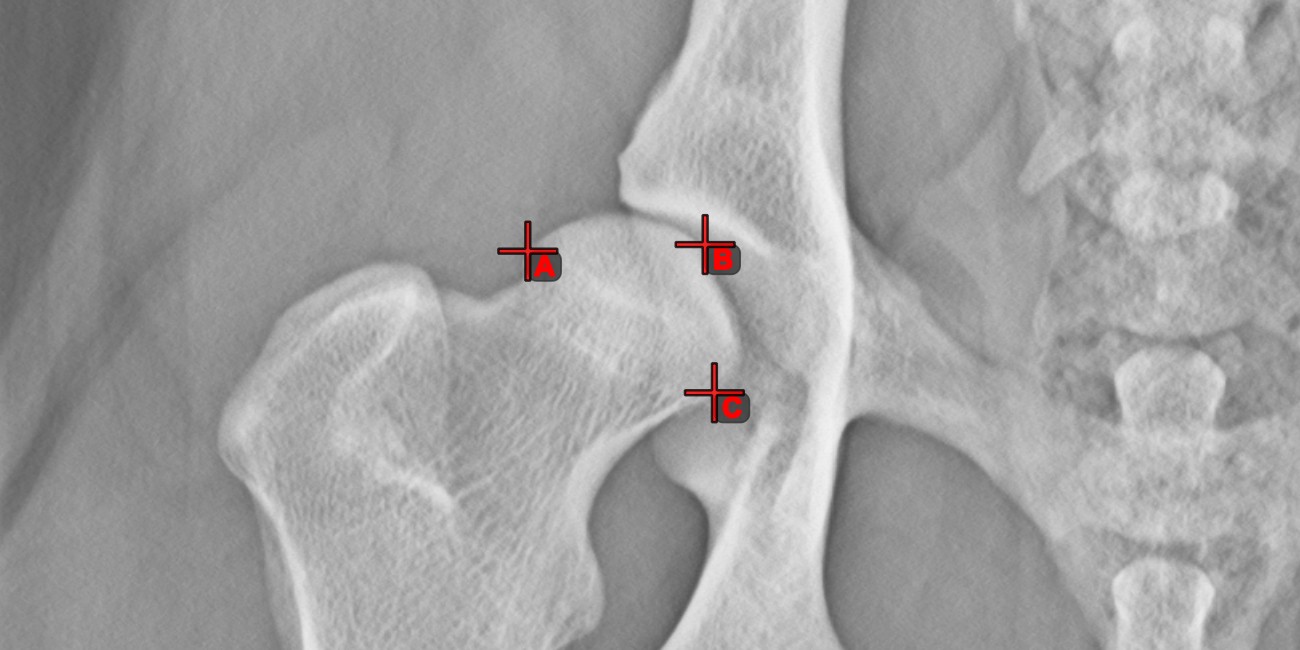

Measurement Point¶

Measurement Point tool. Each point is assigned with a letter for better identification.Select/Move Item tool. Select the point by using the assigned mouse button of the tool, and then move it freely anywhere on the image.